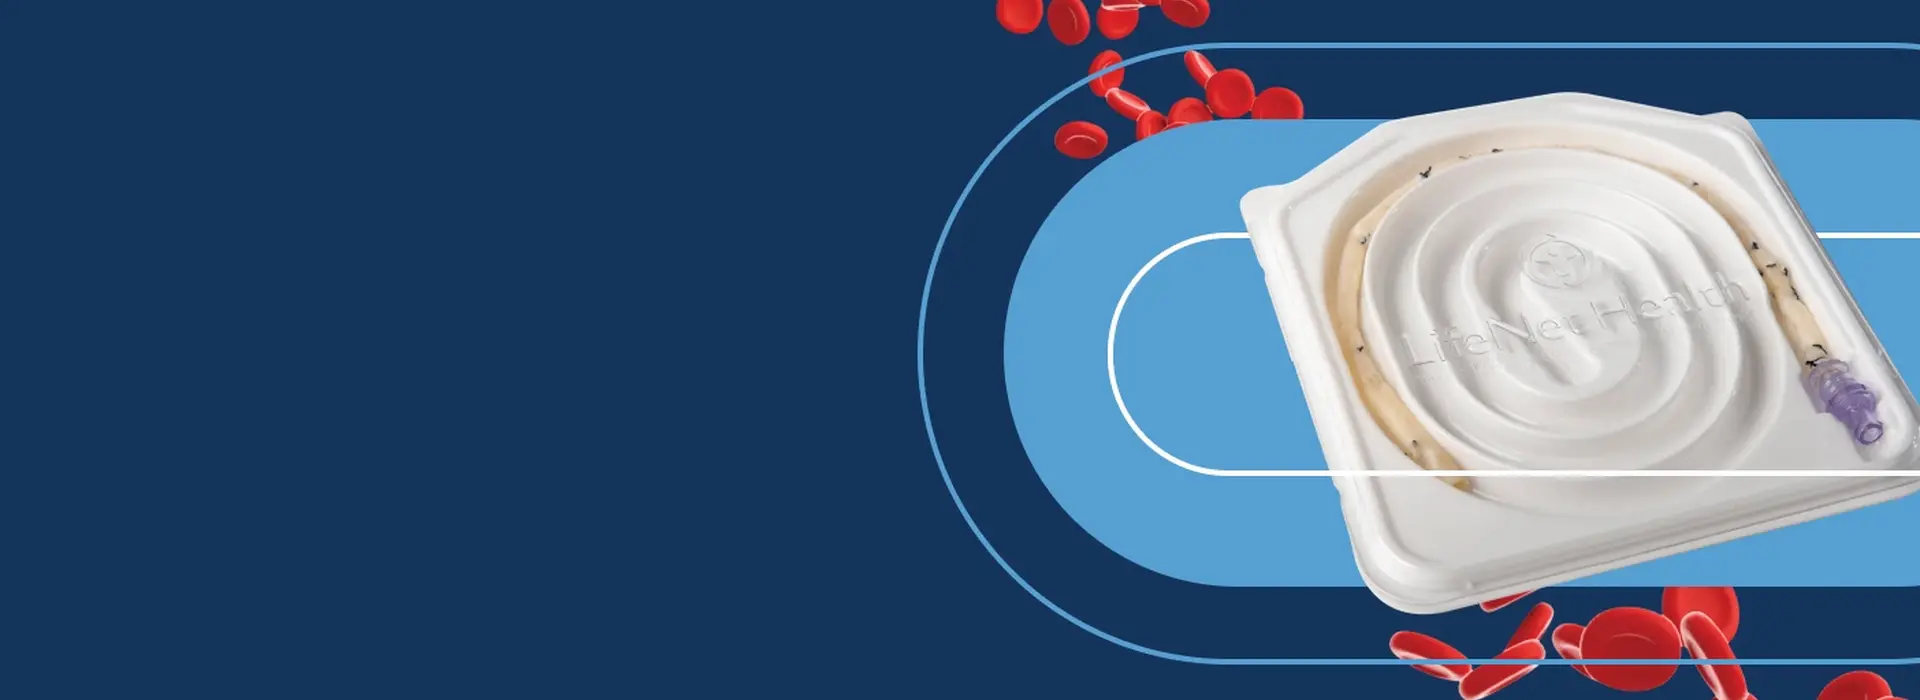

Our full line of allograft bio-implants provides surgeons with the tools they need to improve the lives of patients. From sports medicine to spine, from cardiac and vascular to skin and wound, from craniomaxillofacial to general orthopedics and trauma, our comprehensive portfolio provides surgeons - and their patients - with the right graft for the right procedure. Click on a product icon below for more information on our products and services.